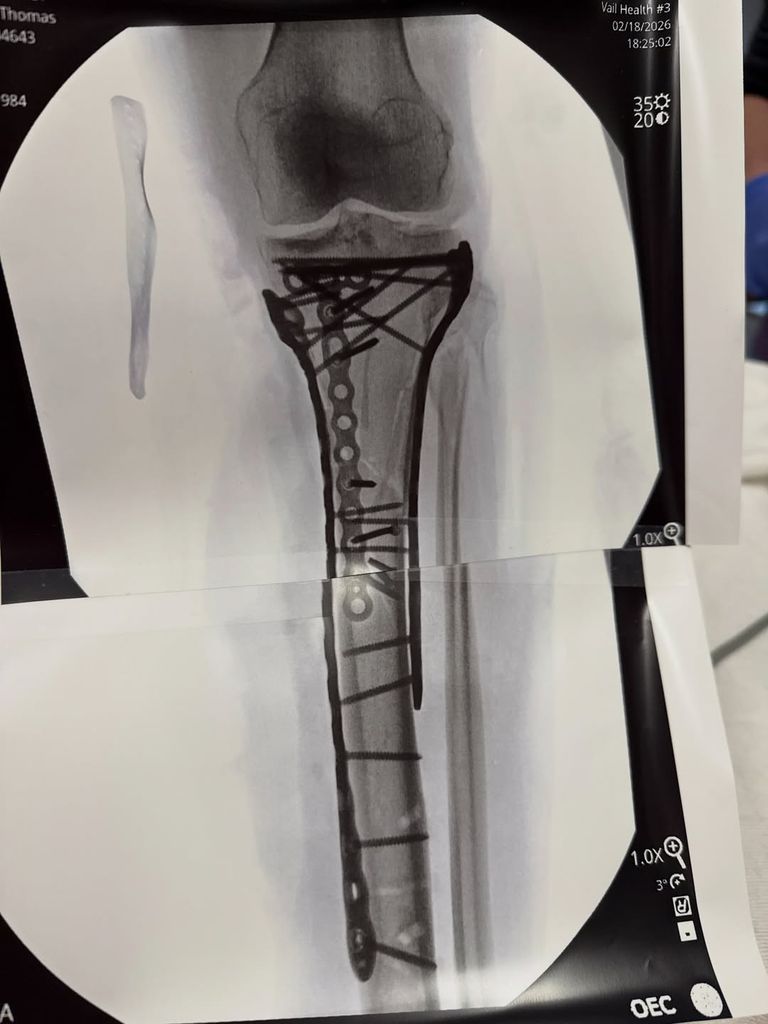

Depuis l’horrible accident, Lindsey a déjà subi cinq interventions chirurgicales correctives, la dernière fois en partageant une mise à jour sur les réseaux sociaux avec un clip d’elle-même transportée au bloc opératoire, ainsi que des scans de sa jambe avec des tiges et des vis déjà en place.

Lindsey Vonn partage une photo d'une radiographie de son tibia fracturé après une opération, partagée sur Instagram©Instagram